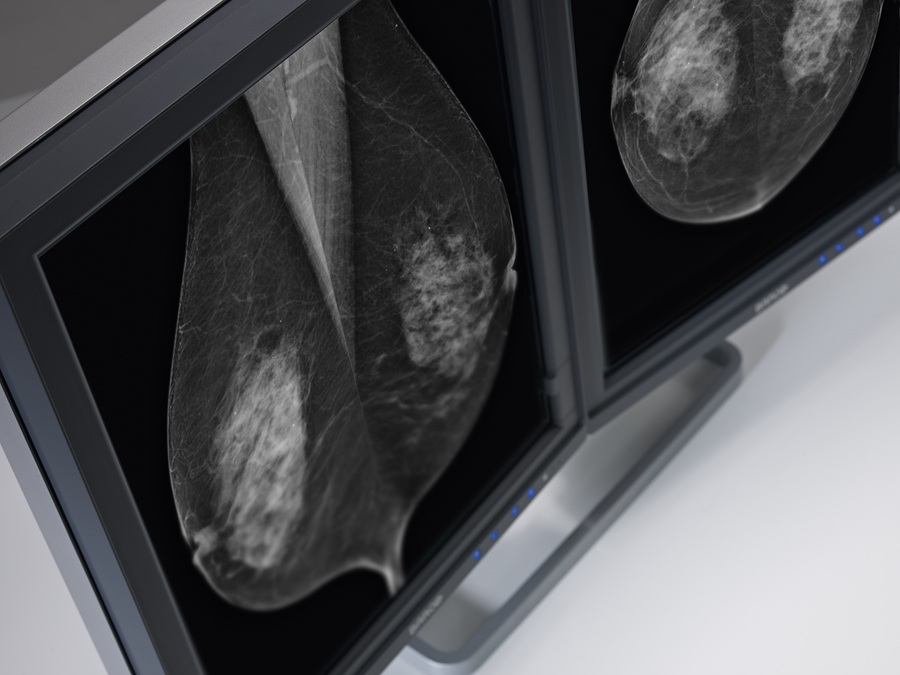

Διαγνωστικές οθόνες υψηλής ευκρίνειας

Οι σύγχρονες εφαρμογές απεικονιστικών ιατρικών διαγνώσεων απαιτούν εξαιρετικής ποιότητας μηχανήματα και οθόνες διάγνωσης, για την απόλυτη απεικόνιση των αποτελεσμάτων.

Η εταιρεία μας προμηθεύει τις υπερυψηλής ευκρίνειας οθόνες για ιατρικά μηχανήματα, της εταιρείας Barco.